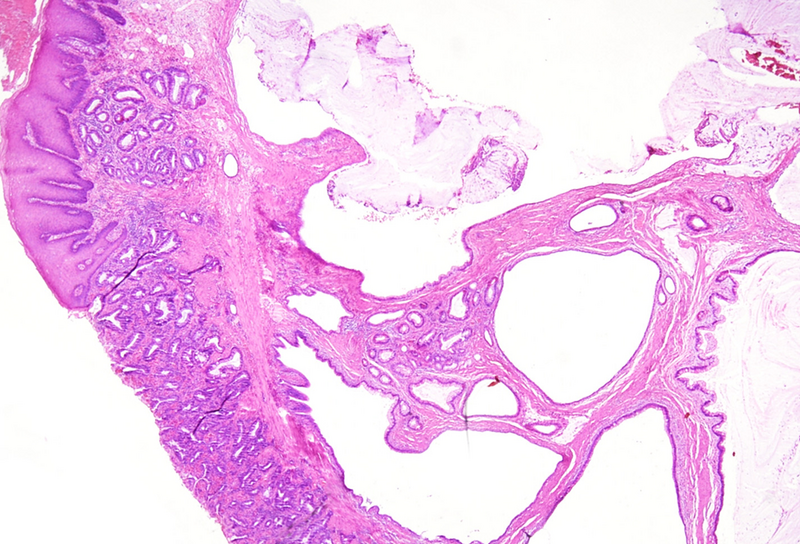

Polypoid lesion at the anorectal junction in a 47 year-old male.

Proctitis cystica profunda.

Microscopically, one specimen disclosed cystically dilated structures of variable size underneath regular colonic  / anal mucosa (Panels A-B). The cysts are filled with mucin, and the epithelial lining is of intestinal type, showing reactive changes, yet no dysplasia in the presence of mixed unspecific inflammation (Panels C-D).

Histologically, it is characterized by the presence of either localised, segmental, or diffuse mucus-filled cysts of the deep submucosa and even muscularis propria. Size of the cysts may differ, depending on localisation and diffuse morphology, lesions can measure up to even 2 cm. The lining epithelium lacks atypia, with only minor nuclear irregularities in case of secondary inflammatory changes. The overlying mucosa is intact. Surrounding areas may contain fibrosis and hemosiderin laden macrophages. The cysts may rupture causing mucin dissemination into the surrounding tissue, potentially followed by degenerative calcification. Differential diagnosis mainly includes mucinous adenocarcinoma, which may be identified by nuclear dysplasia and/or desmoplastic response.